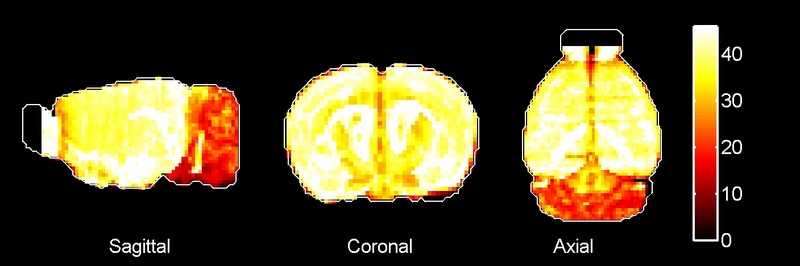

The histograms presented below show the localization scores for this gene for each parcellation: coarse, cortex, & fine. The default setting is relative, which shows the localization score for the gene normalized by the Volume Fraction of the Compartment.

Toggling the 'absolute' button will allow you to see the raw localization scores for each region. Hovering over a bar will reveal the precise localization value - the calculated result of the relative function when the relative button is active, or the raw localization score when the absolute button is active. Additionally, hovering over a specific bar will reveal the relevant brain region on the maps below. Please note that the color of the bars and brain regions are also significant, since they are interpolated on a color scale in accordance to the localization scores.